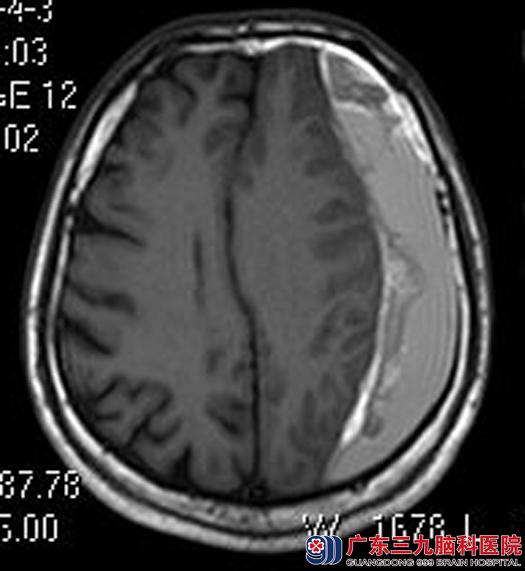

头颅MRI检查显示左侧额颞顶枕部硬膜下血肿(急性与亚急性期混杂)形成伴左侧大脑镰下疝形成。考虑左侧额颞顶部硬膜下血肿尚未全部溶解,先给予活血化瘀等药物治疗。

▲手术前